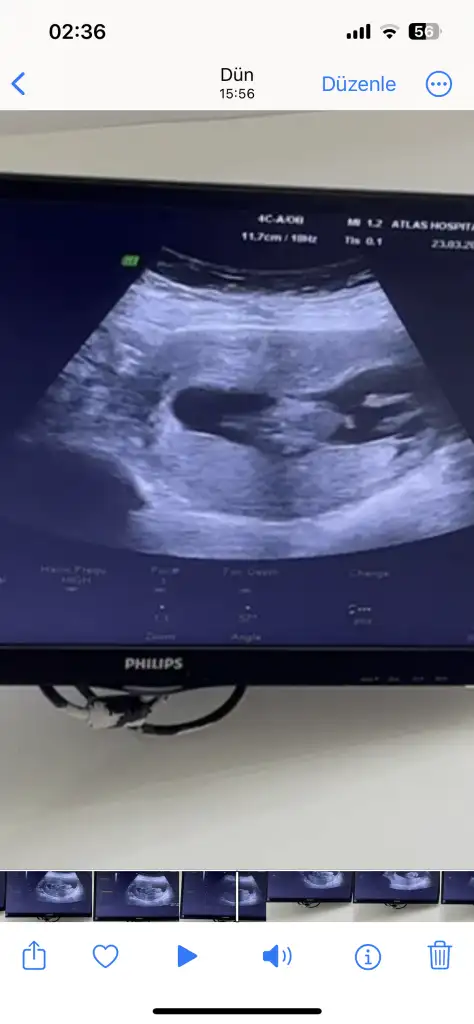

Nub teorisine göre cinsiyet tahmini yapabilen var mııı